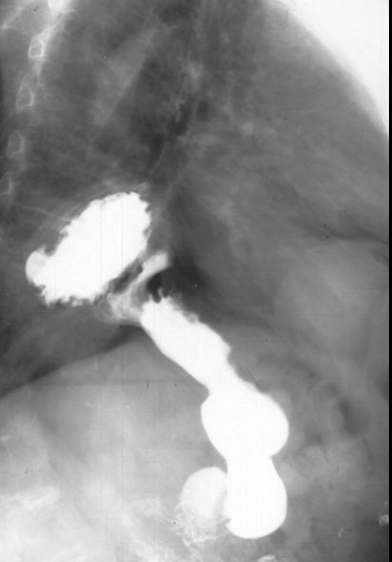

RA of HH on BS or UGI

barium swallow and UGI will show smooth esophagus and stomach with rugae patterns (roughened structure above diaphragm)